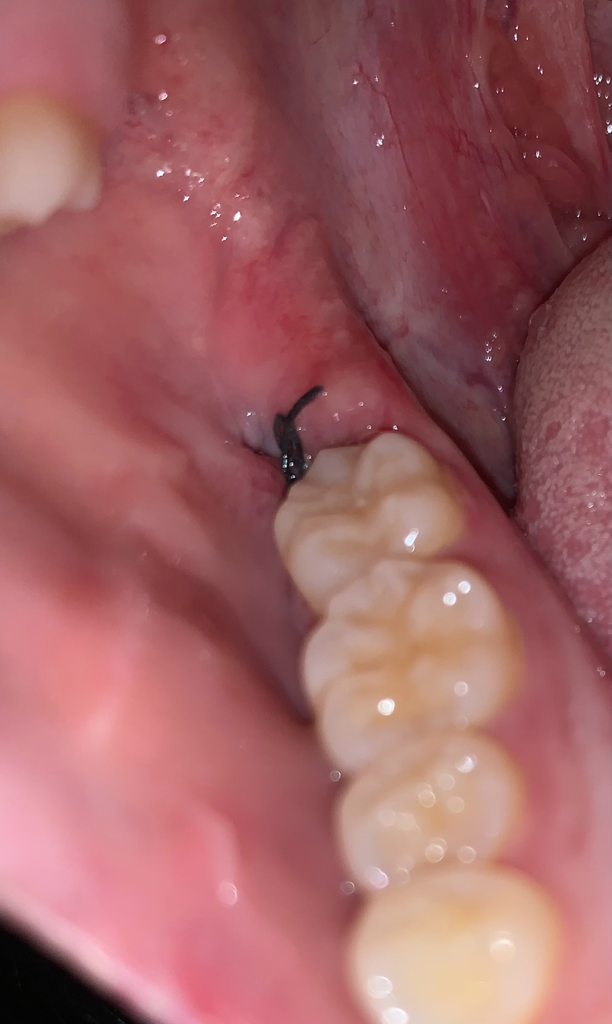

매복사랑니 발치 후 4일차 염증일까요 ?

매복사랑니 발치 4일차인데요

통증이 아예 없는건 아니고 조금씩 있는상태입니다

발치부위가 하얀색 ? 회색인데 괜찮은걸까요??

염증일까요 ? 약 잘 챙겨먹고있는데

사진으로 봤을 경우에는 큰 문제가 없는 것으로 보입니다. 발췌한 부위를 자극하지 않는 것이 좋으며 발한 부위는 이물질이 꼈을 경우 가볍게 가글을 해주는 것이 좋습니다

염증은 없는 것으로 보이며 약간의 통증은 남아있을 수 있는 시기입니다. 하얀막이 생기는 건 정상입니다.

사진상으로는 괜찮아 보입니다 통증은 보통 2~3일차에 심하고 일주일까지도 약간은 지속될 수 있습니다

발치부위 희색물질은 정상 육아조직으로 잇몸 치유과정에서 생기는 것입니다

현재 사진상 문제가 있어 보이지 않으며, 잘 아물고 있는 것으로 보입니다. 7일간은 염증이 덧나지 않아도록 음주 및 흡연은 피하길 권합니다.